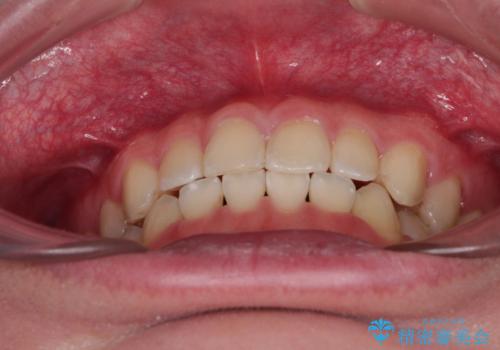

隙間とデコボコを治したい ワイヤー装置による矯正治療

舌の突出癖がなかなか改善されず、治療開始時よりも隙間が大きく開いてしまう時期がありましたが、最終的にしっかりと閉じて終了することができました。